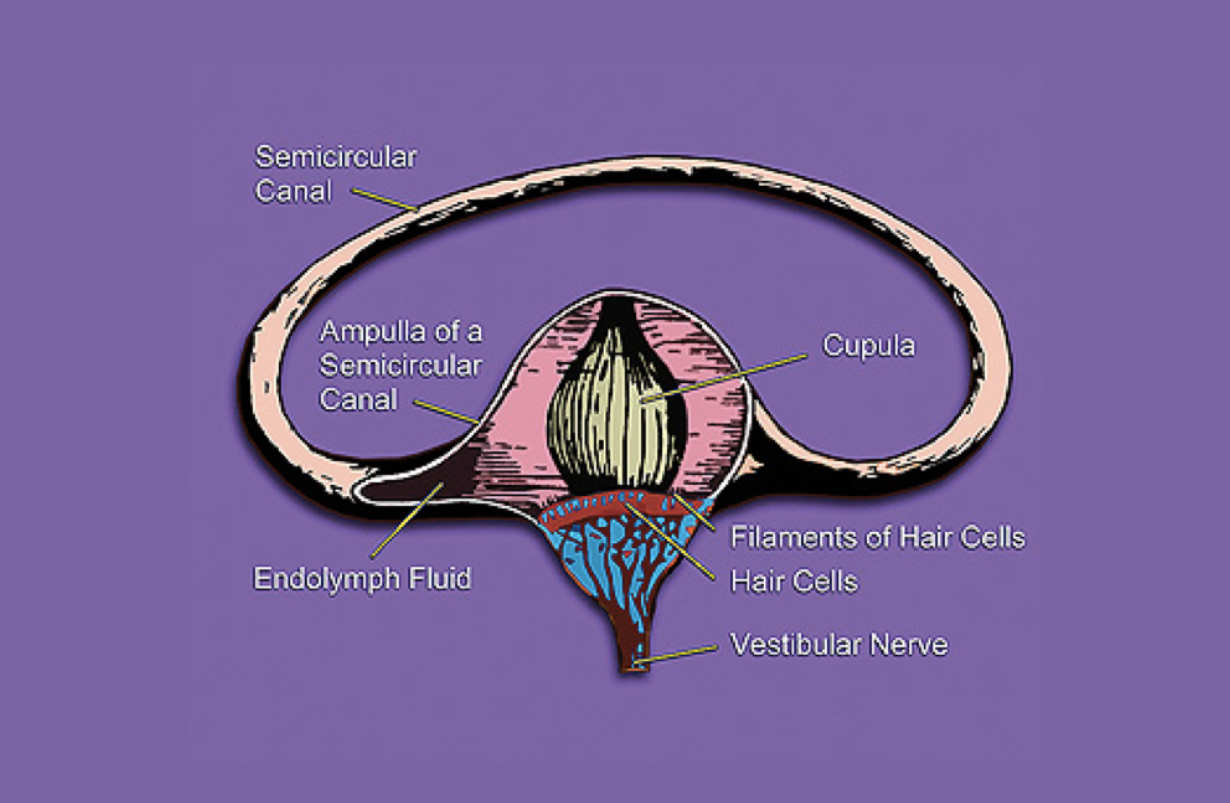

Imbalance

Reduced ability to retain stance or walking without risk of otherwise uncaused faltering or falling

Orthostatic Hypotension

Symptomatic reduction in blood pressure when rising from sitting, e.g., causing fainting or imbalance. BENEFICIAL POSES: Dandasana, Navasana, Tadasana, Vrksasana. EXPLANATION: As infants, when we stand up, our bodies quickly learn to adapt by narrowing the medium-sized blood vessels in our legs, so as not to deprive our brains of blood. As we age, a number of factors can interfere with that adaptation, some remediable through yoga, some not. Neuropathy (neurogenic orthostatic hypotension) , dehydration, and medication (non-neurogenic) are three main causes of orthostatic hypotension, and dizziness and falling are the chief consequences. It is frequently seen in Diabetes and Parkinson’s disease. These poses work by gradually re-instilling the proper responses to our sympathetic and cardiovascular and nervous systems by graded challenges. If they are followed by a general yoga program, graded with respect to vigorousness, people suffering from orthostatic hypotension frequently improve at least somewhat. They must be carefully watched to anticipate and prevent falls. For example, Vrksasana must be done against a wall, with a chair at hand for support REFERENCES: Kanjwal K, George A, Figueredo VM, Grubb BP, Orthostatic hypotension: definition, diagnosis and management..J Cardiovasc Med (Hagerstown). 2015 Feb;16(2):75-81. doi: 10.2459/01.JCM.0000446386.01100.35. Orimo S, Ghebremedhin E, Gelpi E Peripheral and central autonomic nervous system: does the sympathetic or parasympathetic nervous system bear the brunt of the pathology during the course of sporadic PD? Cell Tissue Res. 2018 Jul;373(1):267-286. doi: 10.1007/s00441-018-2851-9. Epub 2018 Jun 4.